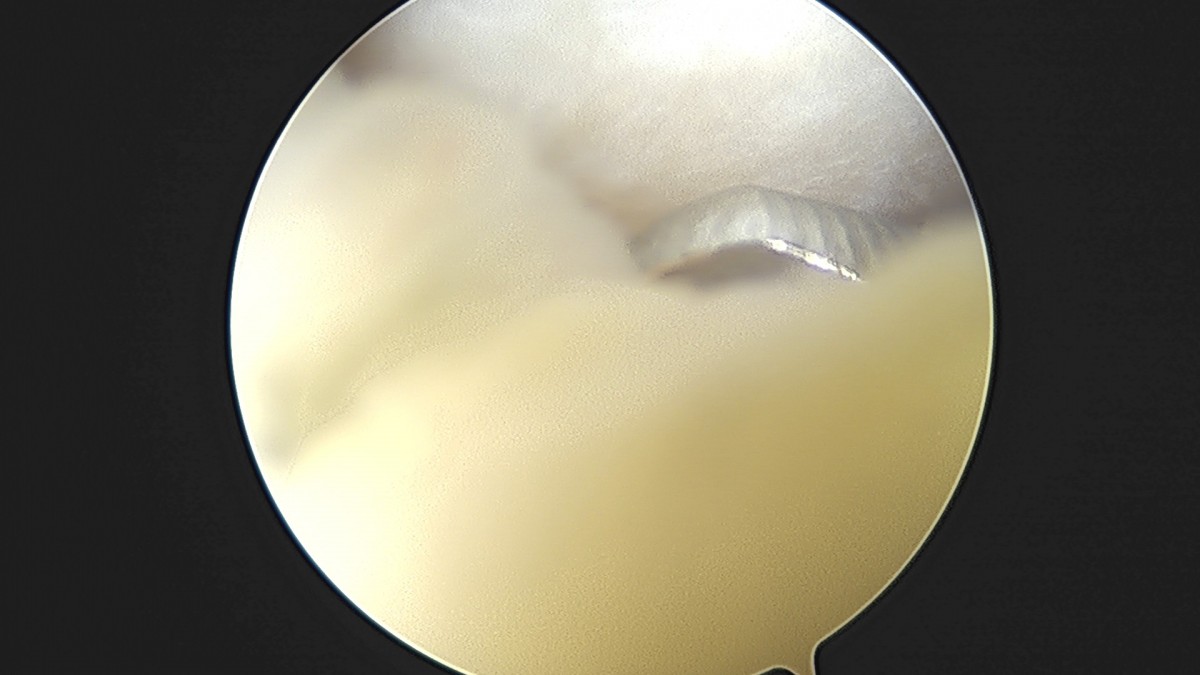

이재상원장님 무릎 반월상 연골판 절제술 박강O 환자

작성자 최고관리자 댓글 0건 조회 381회 작성일 25-09-16 15:47